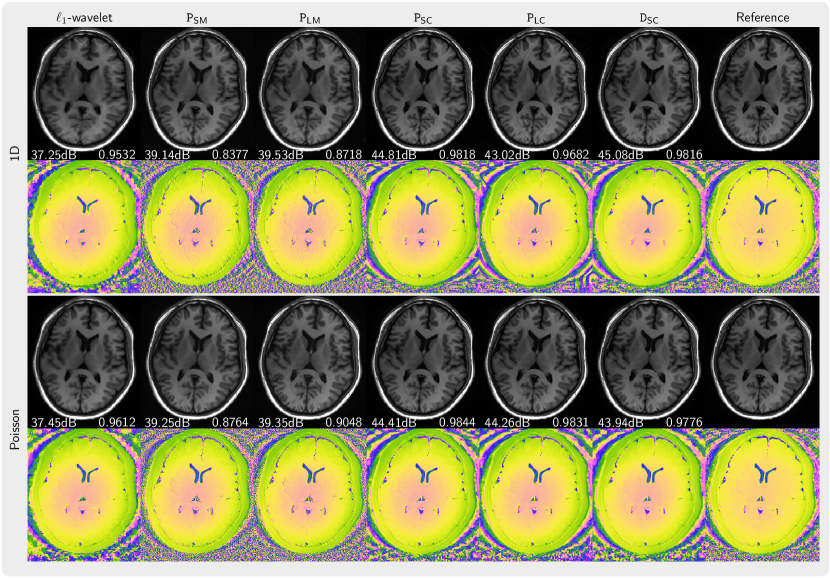

Figure 3 presents the magnitude and phase of images that are reconstructed using PICS with priors trained from magnitude image, complex images with preserved phase, and complex images with generated using our phase augmentation method While the priors PSM and PLM trained from magnitude images can remove folding artifacts introduced by undersampling, they exhibit over-smoothing of the magnitude as indicated by its lower PSNR and SSIM values and also demonstrates poor capabilities in denoising the phase. In contrast, the prior PSC trained on complex-valued images performs much better. Furthermore, the priors PLC and DSC trained on phase-augmented images and perform almost as well. Very similar results were obtained for NLINV as shown in Figure 4. In Figure 5, the k-space is sampled using 2 3 pattern. We observed artifacts (red arrow) introduced by the priors trained from magnitude-only images reconstructed with PICS method, but not with NLINV method. Under all investigated conditions, the priors trained on complex-valued images outperform the reconstruction with -wavelet regularization.